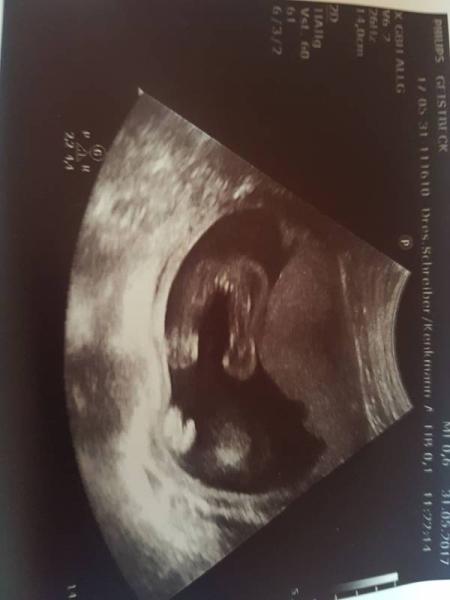

Hallo Ihr Lieben, ich hätte da auch eine Frage zu meinem Ultraschall ich erkenne nichts darauf... Was meint Ihr? Dad bild wurde in der 21 ssw aufgenommen:D

Bild zu